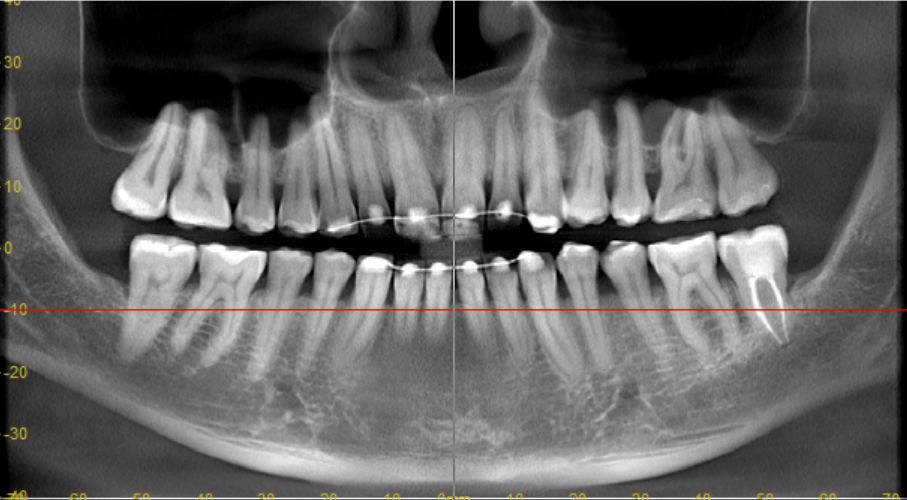

Лол, ты удивишься, чел.. Тем более в провинции где тебе "под ключ" за 300к так пролечат, что потом будешь всю жизнь на таблетки работать